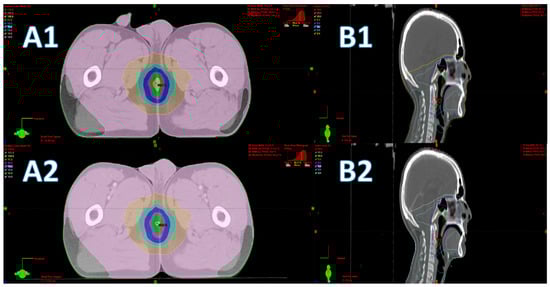

In this study, 3D gamma analysis using local dose comparison method was applied to compare all dose distributions point by point. Unlike global difference point, local comparison is more sensitive to differences in dose calculations [43]. The 3D gamma analysis results revealed that 94% of plans satisfied the recommended 2% and 2 mm criteria, and only 6% of all plans failed the criteria. All 226 patients’ plans, however, satisfied the 3% and 3 mm criteria. Gamma evaluation failures in the 14 patients is attributed to uncontrollable changes in patients’ geometry due to involuntary movements in the lag time between NCCT and CCT scans. Respiratory-induced differences were observed in eight nasopharyngeal patients, one thyroid, and one esophagus cancer patient. Bowel movement-induced differences were observed in two rectum patients, one uterus, and one cervix cancer patient. Two examples for geometry changes are shown in Figure 7; gamma passing rates were reduced because of small movement in body parts and penile displacement in subset A and respiratory movement in subset B. It should be noted that in all treatment plans that did not satisfy the 2% and 2 mm criteria, the dose differences were in low dose regions only which are not clinically significant, and therefore increasing the suppression threshold to 20% was enough to score a satisfactory gamma pass rate with the 2% and 2 mm criteria.

Figure 7. Reduced gamma pass rates in some patients’ plans are the result of patients geometrical differences between NCCT and CCT scans. Subset A shows the difference in geometry due to penile movement, (A1) NCCT, and (A2) CCT. Subset B shows respiratory induced oral cavity movement between NCCT (B1) and CCT (B2).